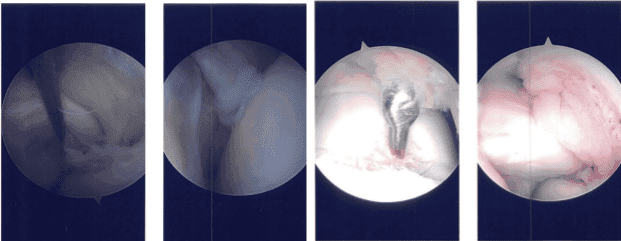

Imágenes de artroscopia intraoperatoria

Se revisó la articulación patelofemoral. La superficie posterior de la rótula estaba prístina, pero había una gran lesión osteocondral de grado 3 a 4 en la troclea.

El menisco lateral mostró una rotura en la parte posterior del cuerpo del menisco lateral, orientado radialmente hacia la periferia. También había una lesión osteocondral de grado 1 a grado 2 en el cóndilo femoral lateral.

Se realizó un portal de entrada medial con acceso directo al menisco lateral. Se introdujeron una afeitadora y mastigadores hacia arriba y se realizó la meniscectomía porque el menisco no podía repararse. Se alcanzaron márgenes estables. Se realizó la condroplastia del cóndilo femoral lateral.

También se realizó la condroplastia de la troclea y se consideró una lesión de grado 4. Se realizó una microfractura. Se podían ver glóbulos de grasa salir. El vestido estaba hecho. El paciente fue trasladado a la zona de detención desde la unidad de cuidados postoperatorios en estado estable tras la extubación.